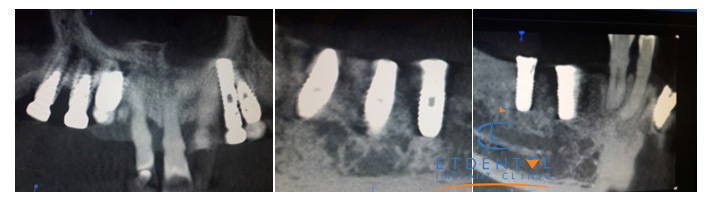

Phim chụp CT 3 chiều sau cắm ghép Implant